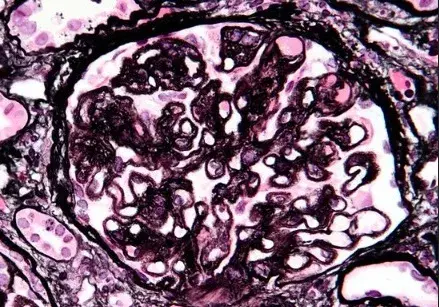

É possível identificar um glomérulo com quebra ruptura da MBG, com crescente celular no espaço de Bowman (seta branca), célula gigante multinucleada (estrela) e ruptura da cápsula de Bowman (seta preta) (PAS; 400×). PAS, ácido periódico-Schiff.

A biópsia renal revelou GN crescêntica necrotizante difusa sem hipercelularidade endocapilar. Alguns raros glomérulos continham células gigantes multinucleadas.

A avaliação da microscopia de luz pode ajudar na diferenciação de casos de **GN por anti-MBG** de casos **GN-ANCA**, já que na GN anti-MBG não observamos hipercelularidade endocapilar e pode ser identificado a presença de células gigantes multinucleadas, estas células gigantes multinucleadas resultam a natureza explosiva e a rápida destruição dos glomérulos observadas em anti-MBG

Desta forma, a presença de lesões crescentes temporalmente semelhantes e células gigantes multinucleadas na microscopia de luz (MO) pode ajudar no diagnóstico precoce.